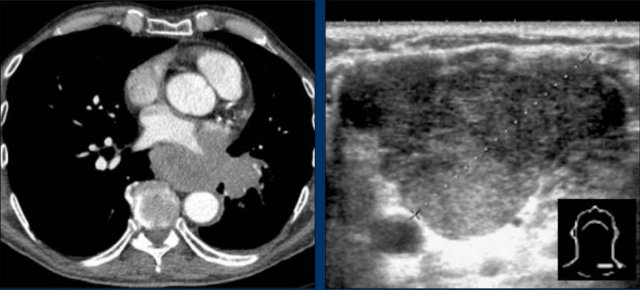

Case Example 1: Pericardial Effusion Mimicking Cardiomegaly

• On the chest radiograph, the patient appears to have a dilated heart.

• However, CT imaging clearly demonstrates that the apparent enlargement is due to significant pericardial fluid accumulation, not true myocardial chamber enlargement.

Case Example 2 - CT imaging

• CT imaging revealed a large posterior pericardial effusion compressing the left ventricle (blue arrow: effusion; red arrow: compressed, contrast-filled left ventricle).

• Surgical exploration confirmed a large posterior pericardial hematoma.

Note

: Minimal anterior fluid on ultrasound may underestimate the true volume if the effusion is loculated posteriorly, highlighting the value of CT in postoperative cases.